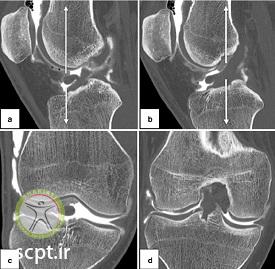

علائمی از فشردگی و کمپرس فراکچر در فمور بخش لترال کندیل آن مشاهده میشود. ( این حالت متفاوت از Deep sulcus sign موجود در رادیوگرافی حالت درازکش قفسه سینه در افراد نموتوراکس است )

در حالتی که جابجایی تیبیا روی فمور بیش از ۷ میلیمتر باشد.

نوعی شاخص شکستگی در محل پروگزیمال استخوان فیبولا که محل اتصال لیگامان آرکوئیت Arcuate ligament complex است.